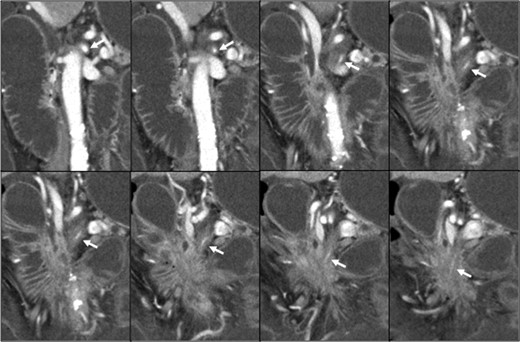

Contrast-enhanced abdominal computed tomography (CT) revealed a 48 × 28 mm mass in the pancreatic head that had invaded the whole circumference of the SMA. The SMA was occluded by the invasion of pancreatic cancer, and almost all of the small intestine was dilated with a very thin wall that was not enhanced (Figs 1 and 2). We diagnosed the patient with peritonitis and extensive necrosis of the small intestine due to SMA occlusion by the invasion of pancreatic cancer.

Pancreatic head cancer invaded the whole circumference of the SMA (white arrow), and the SMA showed stenosis and occlusion.